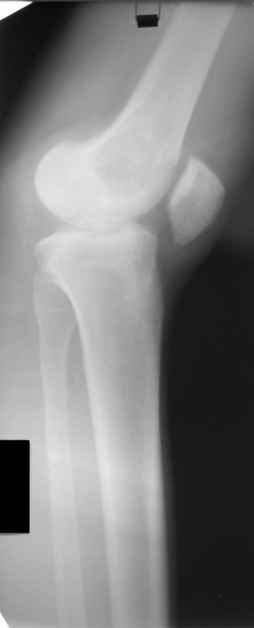

Больной Н., мужчина 18 лет с укорочением бедра и рекурвацией коленного

сустава.